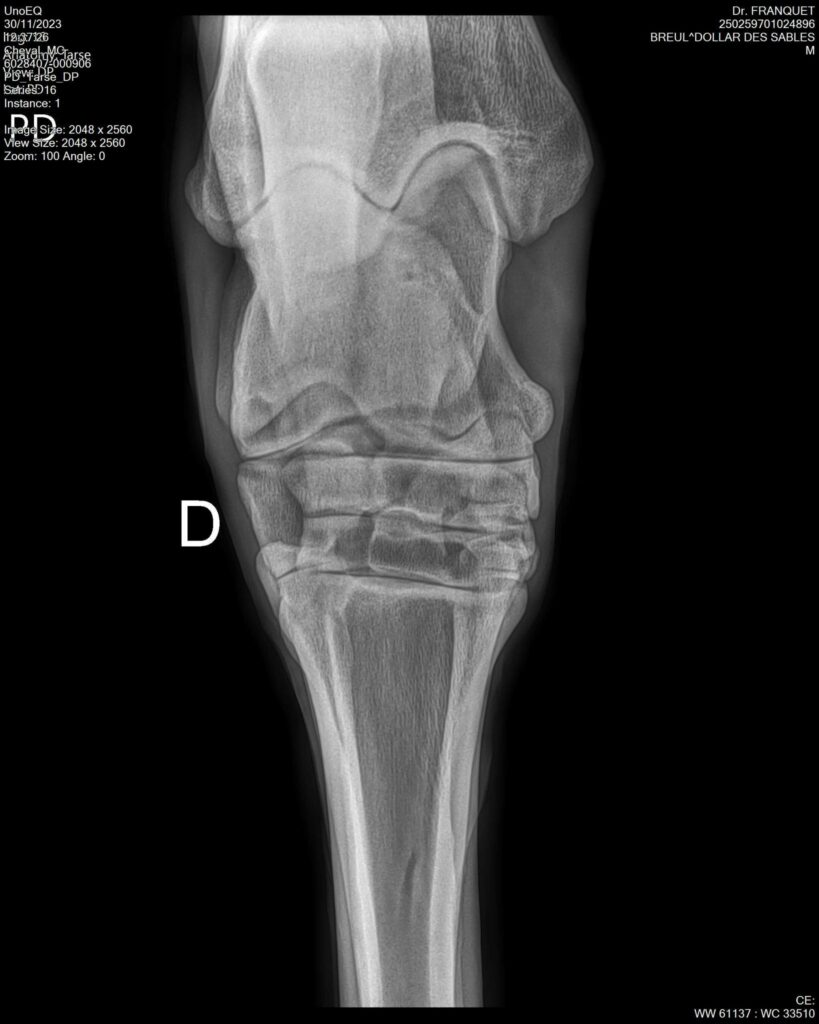

DOLLAR DES SABLES, Selle Français, hongre, 12 ans par DOLLAR DE MURIER x ABKE (ACORADO). Classé 135 avec professionnel à fait 125 avec amateur, récemment classé sur amateur 1GP 120. Très beau modèle ! Gentil cheval, respectueux avec des moyens et du sang. Transport OK, maréchalerie OK, santé RAS, Bilan clichés radios OK.

RADIOS